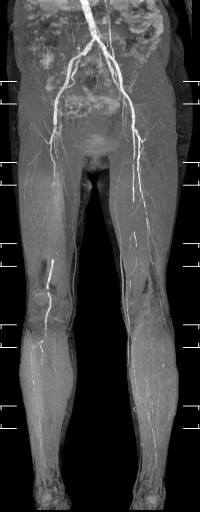

下肢血管画像 (右浅大腿動脈の閉塞と左浅大腿動脈の閉塞の図となります。)